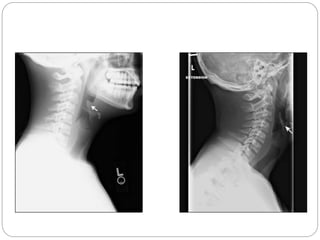

FIGURE 1. Lateral neck radiograph of the patient showed the

classic appearance of supraglottitis: (1) loss of cervical

lordosis,

(2) thick rounded epiglottis (‘‘thumb sign’’), (3) loss of the

vallecular air space, and (4) thickening of the aryepiglottic

folds.

FIGURE 1. Lateralneck radiograph of the patient showed the classic appearance of supraglottitis: (1) loss of cervical lordosis, (2) thick rounded epiglottis (‘‘thumb sign’’), (3) loss of the vallecular air space, and (4) thickening of the aryepiglottic folds.